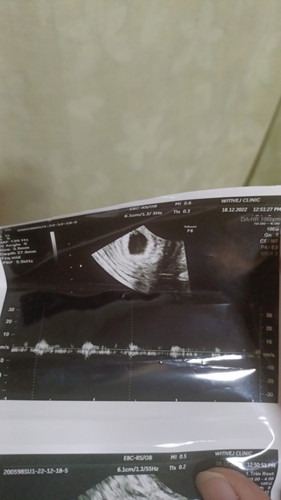

ตั้งครรภ์6W3Dซาวด์เจอถึงไข่แดง และหัวใจเต้น แบบนี้ถือว่าเด็กปลอดภัยหรือยังคะ🥹

ตั้งครรภ์6W3Dซาวด์เจอถึงไข่แดง และหัวใจเต้น แบบนี้ถือว่าเด็กปลอดภัยหรือยังคะ🥹 พอดีเราท้องยาก ก่อนหน้านี้ก็ท้องลมไป

เด็กจะปลอดภัยต่อเมื่อพ้นไตรมาสแรกค่ะ บางเคสเด็กหยุดเจริญเติบโตตอน 10 วีค 13 วีคก็มี

รอจนผ่านไตรมาสแรกไปก่อนถึงจะวางใจได้ค่ะแม่ บ้านนี้อยู่ๆน้องก็หยุดโตตอน13w